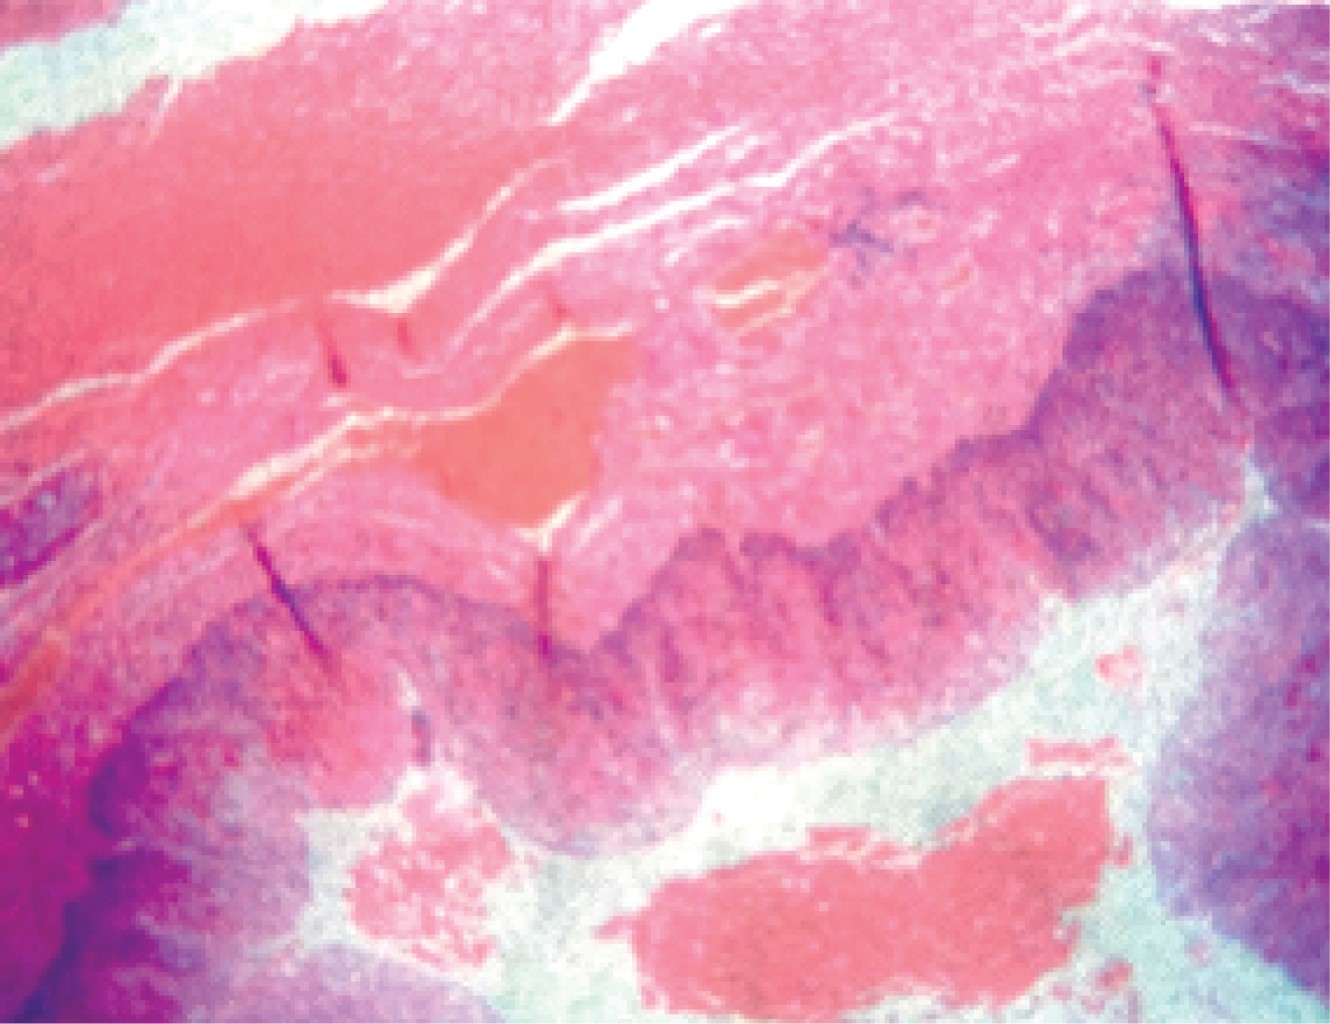

The patient had a good evolution, starting the oral route at 48 hours postoperatively and being discharged at 72 hours; the postoperative diet was managed progressively from liquids to baby food, then soft and finely chopped, to finally continue with a complete diet. Pathology reported the piece as a true diverticulum (Figure 5). In the outpatient follow-up, the patient had an adequate evolution, tolerated the diet, and did not present symptoms of gastroesophageal reflux.

Figure 5